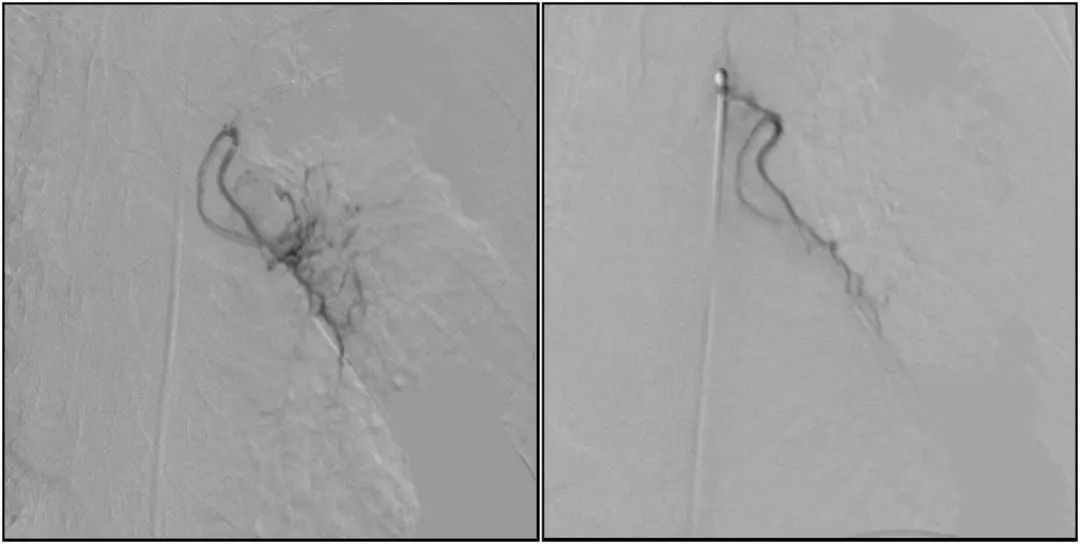

After general anesthesia, an incision was made through the femoral artery. By the image guidance, a micro guide wire is then introduced into the artery and push it up toward the thoracic aorta. After that, superselectively catheterize three tumor blood vessels of left bronchial arteries. By precisely injecting embolic microspheres into the arteries, it successful cut off the blood supply of the tumor.

Before and after embolization